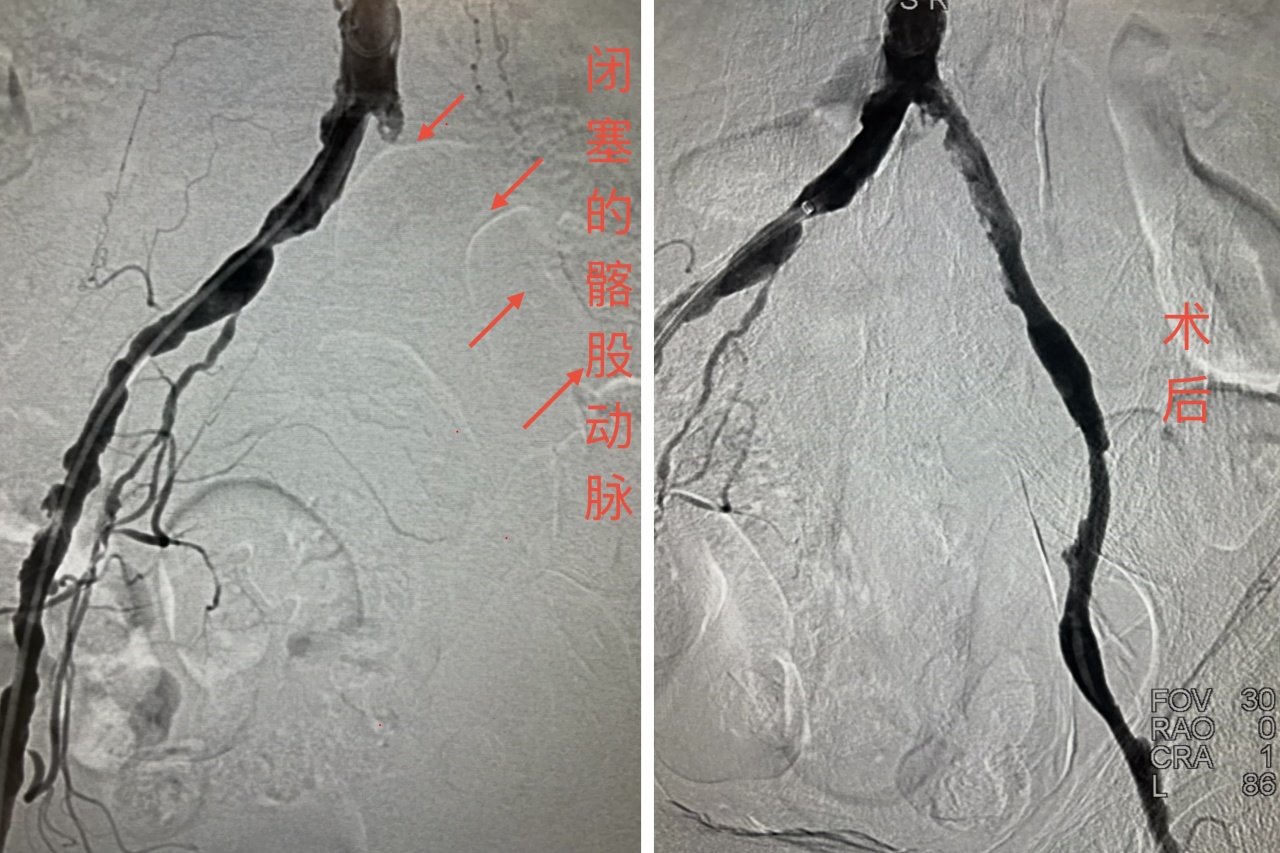

患者为老年男性,因“左下肢疼痛、麻木、无力20余天”从外院转入榆林市星元医院。入院时,患者左下肢青紫发凉、足端发灰,伴趾部溃疡,股动脉、腘动脉及足背动脉搏动均消失,ABI指数为0,急诊CTA确诊为左侧髂股动脉血栓性闭塞,Fontaine分期达3-4期,面临极高截肢风险。

面对紧急病情,介入血管科团队迅速评估,在与家属充分沟通后,果断决定实施“下肢动脉血栓机械旋切清除术”。手术中,团队凭借娴熟的介入技术与丰富的临床经验,精准操作,将堵塞血管的血栓彻底清除,闭塞血管瞬间恢复血流。术后患者左下肢疼痛立即缓解,皮温回升,血运重建良好,肢体得以成功保留。